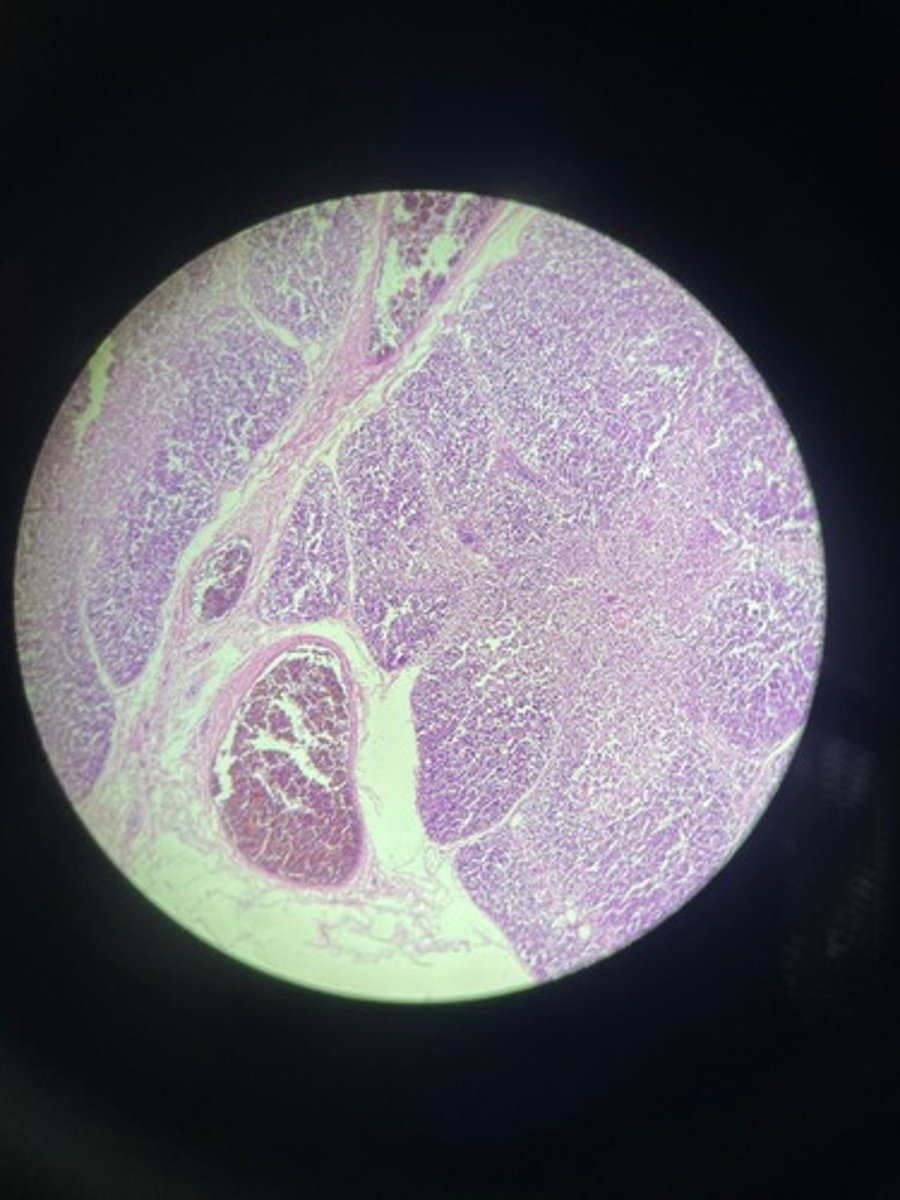

Lymph node HE

Lymph node HE

Lymph node HE

lymph node HE

Lymph node HE

Lymph nodes HE